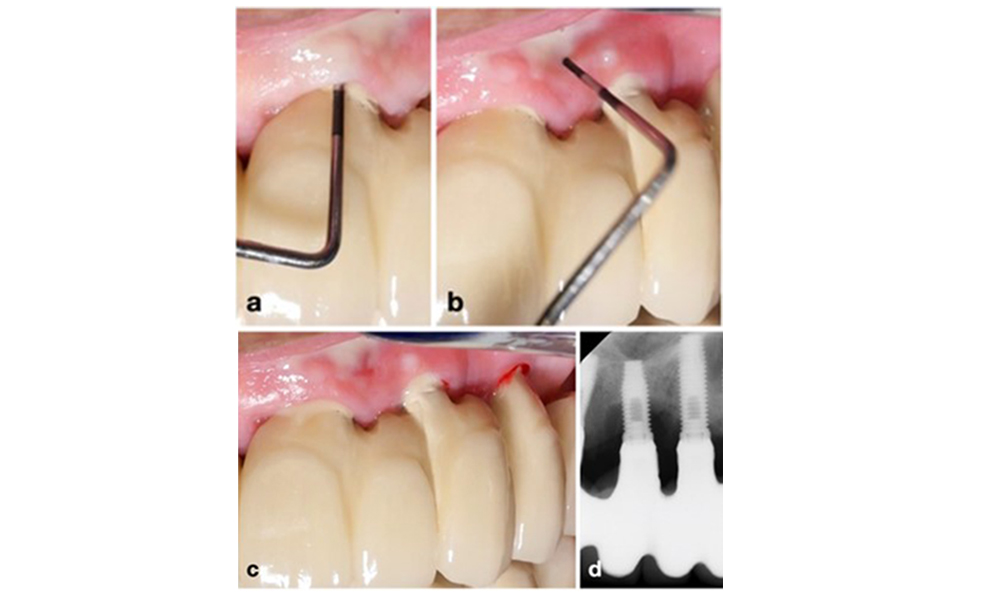

The World Workshop on the Classification of Periodontal and Peri‐Implant Diseases and Conditions from 2017 established diagnostic criteria for peri-implant mucositis and peri-implantitis (Renvert et al. 2018). Peri-implant mucositis is defined as (1) presence of inflammation around the implant (i.e., redness, swelling, line or drop of bleeding within 30 seconds of probing), combined with (2) no additional bone loss after initial healing (figure 1).

Implant in position 26 with peri-implant mucositis (a–c). The probing depth value of 5 mm (b) remains consistent with the measurement taken a few weeks after placing the prosthetic reconstruction. There is bleeding on probing (c) but the radiograph indicates no additional bone loss beyond what is expected for marginal bone remodelling (d).

Figure 1. Implant in position 26 with peri-implant mucositis (a–c). The probing depth value of 5 mm (b) remains consistent with the measurement taken a few weeks after placing the prosthetic reconstruction. There is bleeding on probing (c) but the radiograph indicates no additional bone loss beyond what is expected for marginal bone remodelling (d).

Peri-implantitis is identified by (1) signs of inflammation similar to mucositis, (2) radiographic evidence of bone loss after initial healing and (3) an increase in probing depth compared to measurements taken shortly after placing the prosthetic reconstruction (figure 2). In the absence of previous radiographs, radiographic bone level of ≥ 3 mm along with bleeding on probing and probing depths ≥ 6 mm, indicates peri‐implantitis.